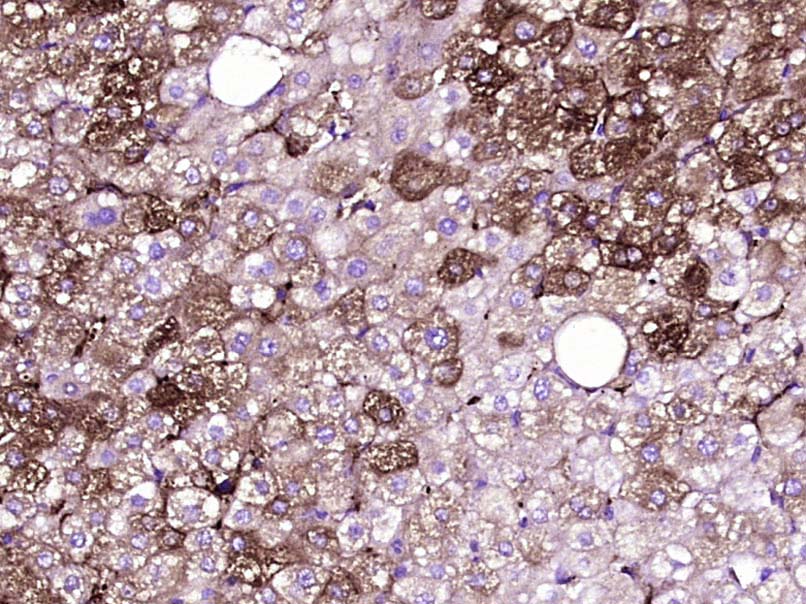

Paraformaldehyde-fixed, paraffin embedded Human liver cancer; Antigen retrieval by boiling in sodium citrate buffer (pH6.0) for 15min; Block endogenous peroxidase by 3% hydrogen peroxide for 20 minutes; Blocking buffer (normal goat serum) at 37°C for 30min; Antibody incubation with _x000D_ JAK1 Monoclonal Antibody, Unconjugated (bsm-33268M) at 1:400 overnight at 4°C, DAB staining.

ApplicationsImmunoFluorescence, ImmunoCytoChemistry, ImmunoHistoChemistry, ImmunoHistoChemistry Frozen, ImmunoHistoChemistry Paraffin

- Applications SupplierIHC-P(1:200-400), IHC-F(1:100-500), IF(ICC)(1:50-200), IF()